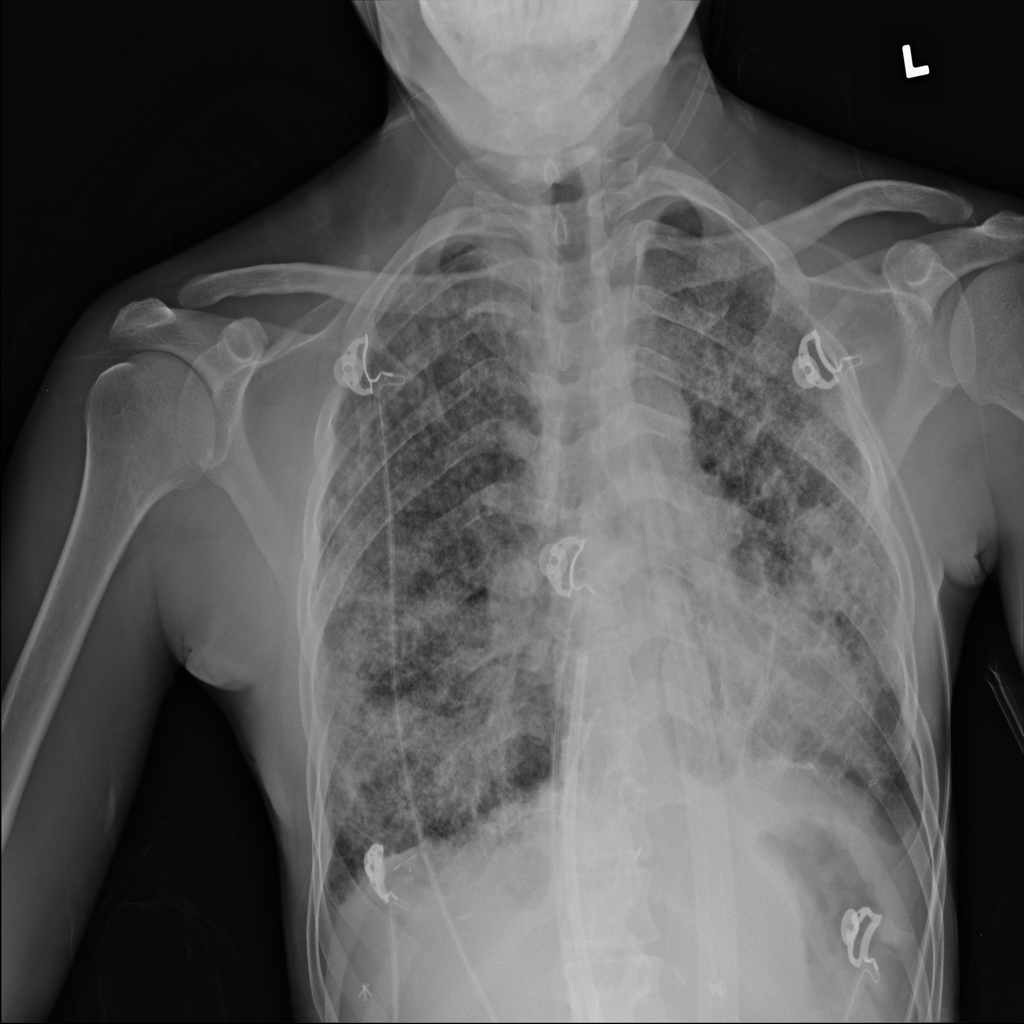

PAT-4639 · IMG-011Pneumothorax

PAT-4639 · IMG-011

AP